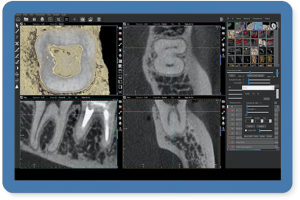

A empresa criou um sistema de radiologia odontológica que proporciona imagens realistas, oferecendo um nível de detalhamento profundo, permitindo a interpretação correta, eficaz e rápida do profissional. “O resultado final é surpreendente. Incrível. Já temos feedbacks extremamente positivos de profissionais renomados em todo mundo”, comenta do criador da empresa, Roney Rocha.

Entre os produtos oferecidos pela CDT Software é o E-VOL DX, reconhecido por pesquisas acadêmicas nacionais e internacionais de odontologia, possibilita imagens mais nítidas e com maior riqueza de detalhes! “O e-Vol DX é um software que supre demanda dos tradicionais aparelhos de radiologia. Compatível com os principais equipamentos do mercado, ele é composto por filtros e ferramentas que transformarão seus laudos”, ressalta.

Além disso, o e-Vol DX está em constante atualização para atender e antecipar-se às demandas dos profissionais da área de radiologia odontológica. Por isso, é um investimento seguro e eficaz e que não estará defasado. Com todos os recursos que garantem obter as melhores imagens de seu tomógrafo, o e-Vol DX possibilita otimizar o tempo de produção com o uso de ferramentas exclusivas.